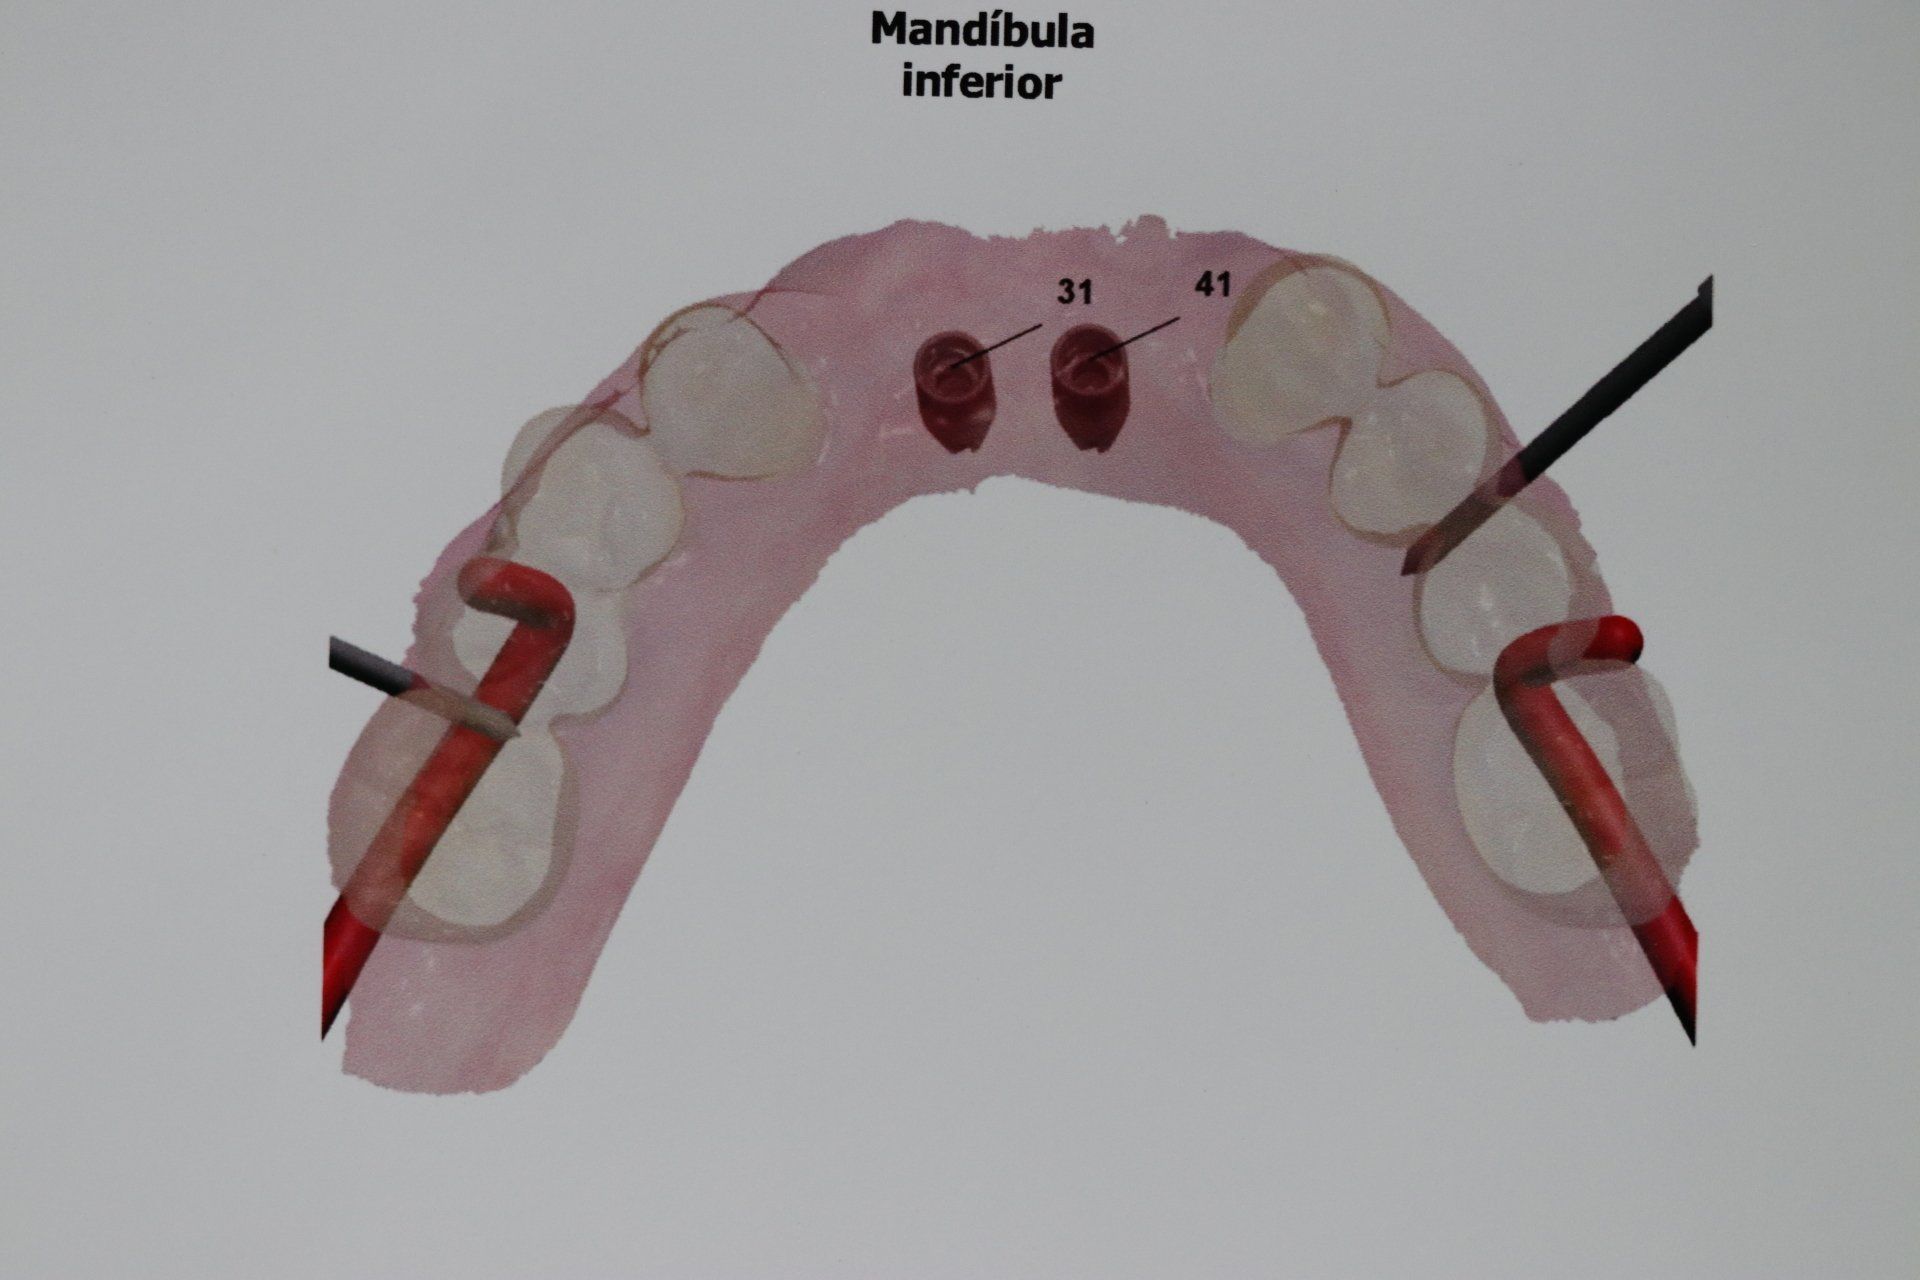

O Implante Dental é um tratamento de Odontologia para reposição dos dentes irrecuperáveis por meio de cirurgias e tratamentos ósseo integráveis.

As imagens apresentadas são apenas ilustrativas do que pode ser conseguido com alguns tratamentos odontológicos, não demonstrando garantia de resultados. Cada situação particular exige diagnóstico e planejamento adequados e individualizados.